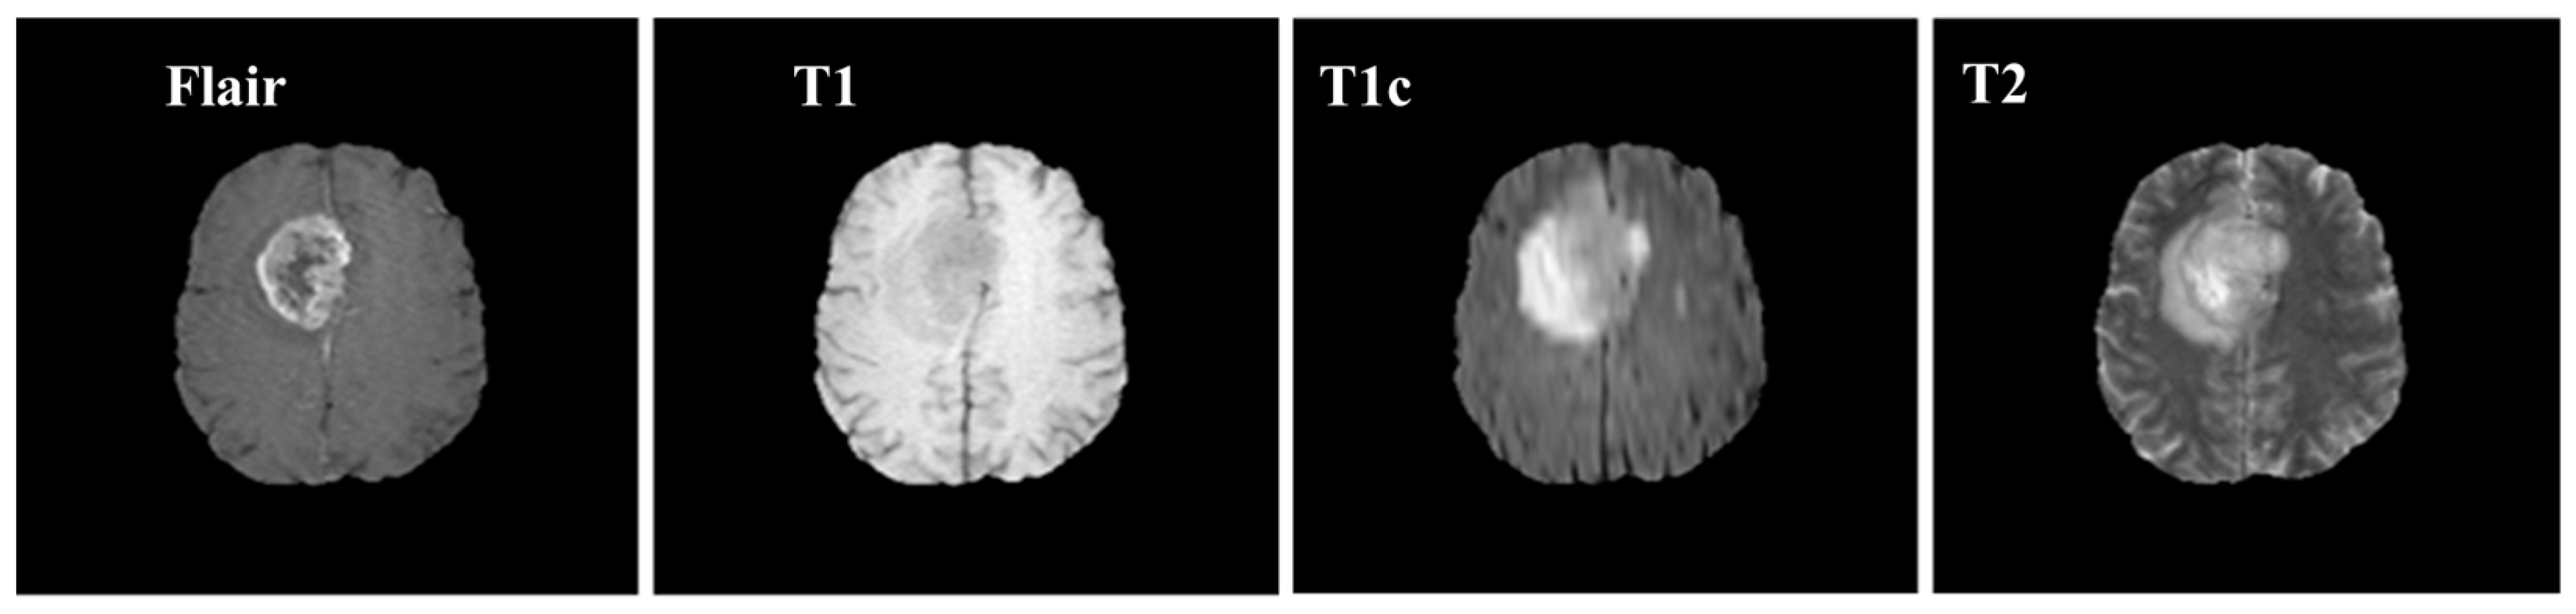

Brain MRI tumors have complicated structures and shapes, which makes the tumor classification and segmentation process more difficult using uni-modality. MRI machines provide an option to capture multimodality images with a more detailed representation of brain tissues [9]. During the MRI scan of a patient, the MRI machine produces different types of MRI sequences including T1, T2, T1c, and Flair, which are based on the Time to Echo (TE), Repetition Time (TR), brightness and contrast values. Figure 3 describes the four different brain MRI modalities and Figure 4 describes the three different types of healthy tissues inside the brain.

Samples of these four modalities (T1, T2, T1c, Flair) are presented in Figure 6. All four modalities have 620 MR images which make a total of 239,320 MR images for all 384 cases and a total of 169,880 MR images 274 train images as shown in Table 2. In BraTS dataset, labels are provided only for the train images so only train images are used for experiments. The dataset is divided into 60% for training, 20% for validation and 20% for the testing. BraTS provides data in MetaImage (.mha) format which is used to store 3D medical images. For each modality of every case, there are 155 slices with 240 × 240 pixel dimensions which are stored in a single mha file.

Figure 3. Pictorial view of brain MR Image modalities.

Figure 6. Sample MR images of T1, T2, T1c and Flair modalities.